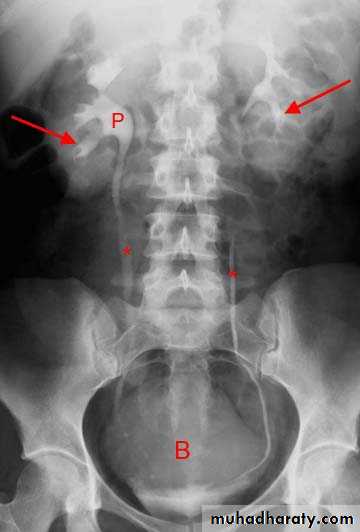

IVU

Normal excretory phase of an IVU (intravenous urogram). This film was taken approximately 10 minutes following IV injection of iodinated contrast material. The kidneys are excreting contrast into non dilated calyces (arrows), renal pelvis (p), ureters (*) and bladder (B).